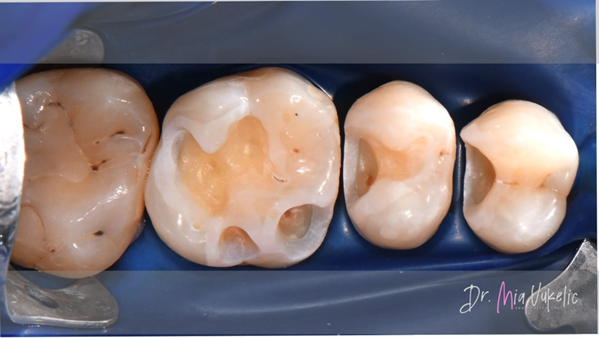

Für die Wiederherstellung der Approximalwand kamen Halo™ Matrizen und Ringe (Ultradent Products) zum Einsatz.

Dabei wurde eine modifizierte zentripetale Aufbautechnik eingesetzt. Im ersten Schritt wurde eine Schicht fließfähiges Komposit (Tetric EvoFlow™, Ivoclar*) mit einer Stärke von 0,5 mm aufgetragen.

Das Mittel der Wahl für die Restauration war Transcend™ Universalkomposit (Ultradent Products). Die Approximalwand wurde mit der Farbe EW erstellt. Für die beiden folgenden horizontalen Schichten wurde die Farbe A3D verwendet. Sekundärcharakteristika wurden mit dem Kolor + Plus™ Farbmodifikator – braun (Kerr*) erzielt.